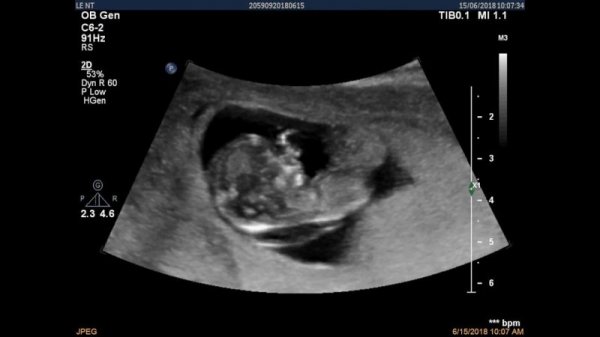

Siêu âm giúp bác sĩ dễ dàng quan sát tình hình phát triển của thai nhi, nhưng siêu âm đầu dò có ảnh hưởng đến thai nhi không? (ảnh: pinterest.com)

Với phương pháp này, bác sĩ có thể kiểm tra và chẩn đoán được sự phát triển của thai nhi hay những sự bất thường của thai nhi thông qua các chỉ số mà đầu dò thu được và hiển thị trên màn hình. Qua đó, khi thai nhi hay cơ thể mẹ xuất hiện những tình huống bất thường, thông qua siêu âm, bác sĩ có thể kịp thời phát hiện và có phương pháp điều trị phù hợp.

Trong Y học chưa có bằng chứng nào cho biết siêu âm nhiều có tốt cho thai nhi không? Bởi về bản chất, siêu âm là sử dụng sóng âm thanh có tần số cao chứ không sử dụng các công nghệ nguy hiểm khác nên hoàn toàn không có hại.